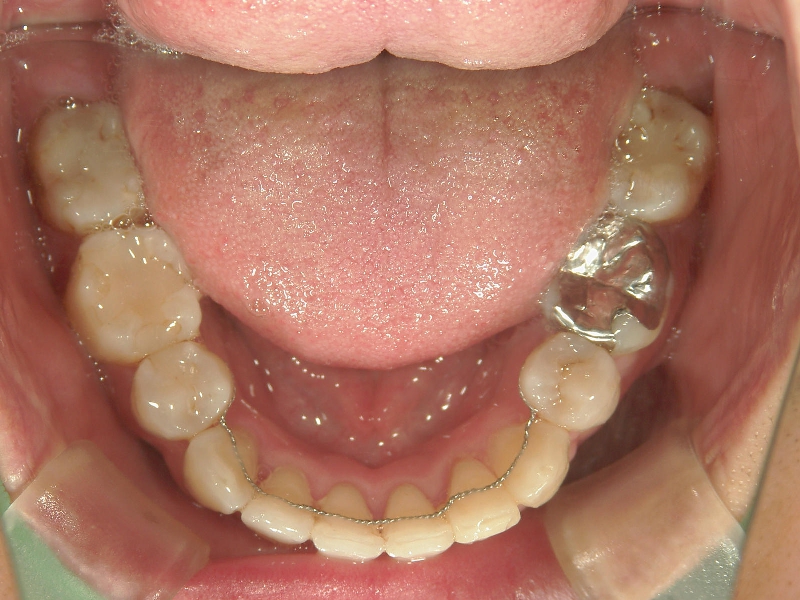

矯正歯科 治療後

矯正_灰色.pngno.31_1962_治療後_下.JPG矯正_灰色.png